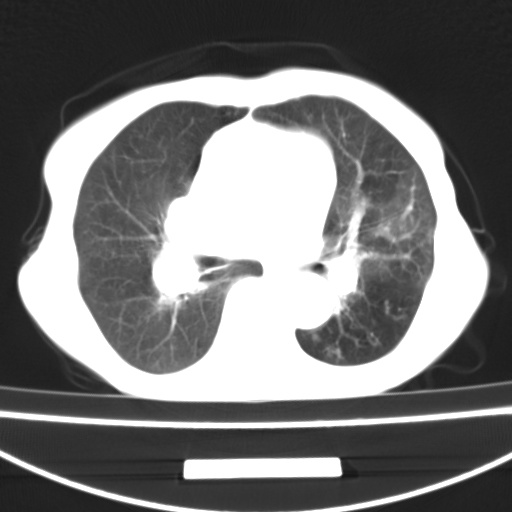

患者 女 67岁,反复咳嗽咳痰2年,加重伴喘及双下肢浮肿1月

诸大血管及f肺门血管增粗迂曲.左下肺多发薄壁空腔影.部分非也透亮度增高.薄曾扫描可区分肺气肿类型.考虑1.慢性支气管炎 2.左下肺支气管扩张 3.肺气肿 4 肺动脉高压5.是否有先心病病史

考虑1.慢性支气管炎 2.左下肺支气管扩张 3.肺气肿 4 肺动脉高压

慢支炎、肺气肿、双肺感染、左下囊状支扩。

慢支、肺气肿、肺动脉高压;左下肺囊状支扩并粘液栓形成。